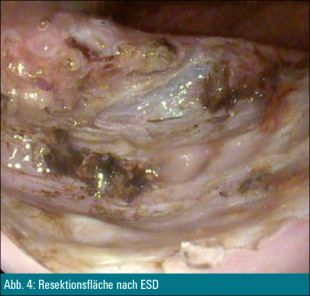

Die Läsion wurde mittels endoskopischer Submukosadissektion abgetragen (Abbildung 4). Das histologische Ergebnis war ein differenzierter neuroendokriner Tumor des Rektums: G1, pT2, L0, V0, R0.